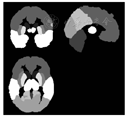

数据均使用SPM8(http://www.fil.ion.ucl.ac.uk/spm/software/spm8/)、VBM8工具箱(http://dbm.seato.uni-jena.de/vbm8/)进行处理。(1)组织分割:使用自定义的Dartel脑分割模板(图1),对入组及2年后随访时的所有被试者的原始T1加权像图像进行分割处理,得到蒙特利尔神经学研究所(MNI)标准空间下各被试灰质和其他组织的图像及原始空间下各被试灰质、白质和脑脊液的图像。(2)平滑处理:用8 mm半高全宽高斯核平滑对脑白质体积图进行平滑。(3)脑白质体积的提取:选取FSL(https://fsl.fmrib.ox.ac.uk/fsl/fslwiki/)软件中自带的脑叶模板MNI-maxprob-thr0-1mm.nii,依次提取各脑叶,使用ANTS(http://picsl.upenn.edu/software/ants/)软件进行配准,制作自定义的脑叶模板(图2),分别提取每个被试者的额叶、颞叶、顶叶、枕叶、左右大脑半球的白质体积及全脑体积。